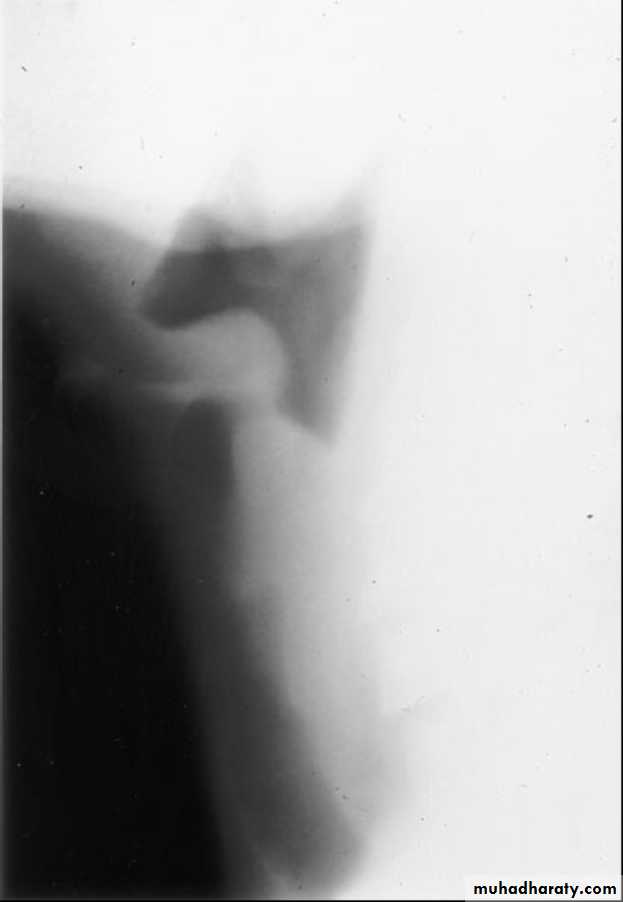

Q 10/ A previously healthy 2-year-old black child has developed a chronic cough during the previous 6 weeks. He has been seen in different emergency rooms on two occasions during this period and has been placed on antibiotics for pneumonia. Upon auscultation, you hear normal breath sounds on the left. On the right side, you hear decreased air movement during inspiration but none upon expiration. Inspiratory (A) and expiratory (B) radiographs of the chest are shown below. Which of the following is the most appropriate next step in making the diagnosis in this patient?

A

B

Recurrent pneumonias in an otherwise healthy child should suggest the potential for anatomic blockage of an airway. In the patient in this question, the findings on clinical examination suggest a foreign body in the airway. Inspiratory and expiratory films can be helpful. Routine inspiratory films are likely to appear normal or near normal (as outlined in the question and noted in the first radiograph). Expiratory films will identify air trapping behind the foreign body (as noted on the second radiograph). It is uncommon for the foreign body to be visible on the plain radiograph; a high index of suspicion is necessary to make the diagnosis. Suspected foreign bodies in the airway are potentially diagnosed with fluoroscopy, but rigid bronchoscopy is not only diagnostic but also the treatment of choice for removal of the foreign body.